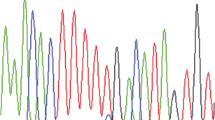

Mutational analyses of K-RAS (exons 1 and 2) and EGFR (exons 18–21) were performed as previously described [26, 27]. Primer sequences are listed in Supplemental Table 1.

A total of 57 tumor tissues were available for additional molecular and immunohistochemical tests (Supplementary Tables 2 and 3), depending on the DNA quality and the size of the tumor samples. Fluorescence in situ hybridization (FISH) revealed amplification of c-MYC (up to ten signals per nucleus) in one case, low-level amplifications (between five and seven signals per nucleus) in 6 cases and a normal c-MYC copy number in 34 tumor samples. Immunohistochemical stains showed diffuse expression of DCC in non-neoplastic tissues. In contrast to this, 17 of 56 available tumors (30.4 %) showed complete loss of DCC expression, and 27 tumors (48.2 %) revealed significant reduction of DCC expression, displaying only very faint staining intensities. Only 12 tumors (21.4 %) showed regularly maintained DCC immunoreactivity, comparable to that in non-neoplastic tissues. Microsatellite instability was detected in 2 of 42 informative tumor tissues, revealing MSI in at least 2 of 3 markers. No tumor revealed MSI of only one marker. Aberrant expression of the mismatch repair gene products MLH1, MSH2, and MSH6 was not observed. In one of the microsatellite unstable tumors, MSH6 staining was considered not informative because of the complete absence of staining in tumor and control tissue. Additional PMS2 staining in the two microsatellite unstable tumors revealed lack of nuclear PMS2 expression in case 40, suggesting a PMS2 deficiency as cause of the MSI phenotype, and a reduction of PMS2 staining compared to surrounding non-tumorous cells in case 10. Mutational analyses of K-RAS comprising exons 1 and 2 revealed mutations in 2 of 41 tumor tissues tested (2 %), affecting codon 12 (GGT 12 GAT) and codon 13 (GGC 13 GAC) (Fig. 4). Membranous immunohistochemical expression of EGFR was observed in 19/45 tumors (42 %), with positive tumor cells ranging between 80 and 100 % in 14 cases, 40 % in 1 case, and 5 % in 4 cases. There were no EGFR mutations found in exon 18 (41 informative cases), exon 19 (n = 40), exon 20 (n = 31), and exon 21 (n = 26). Immunostaining with the BRAF mutation specific antibody V600E or with Her2/neu was negative in 42 tumors. Loss of nuclear MGMT expression was lost in 13/51 tumors (26 %) (Fig. 5). High immunohistochemical expression of L1CAM was recognized in 39/54 tumors (72 %), with diffuse staining in 29 cases and focal staining in 10 cases. Finally, cytoplasmic HSP90 expression was observed in 47/48 cases (98 %). Seven cases, including one cytoplasmic-negative tumor, showed nuclear HSP90 immunoreactivity. There were no significant differences between PACs and MACNECs. None of the above molecular findings correlated with the cytogenetic clusters.

Molecular and immunohistochemical characteristics of PACs: a FISH analysis showing c-MYC amplifications; b immunohistochemical loss of DCC expression in liver metastasis (regular DCC expression in adjacent liver tissue, depicting red); c PAC (case 40) with loss of PMS2 expression in tumor cells, while intratumoral lymphocytes show regular nuclear PMS2 positivity (depicting red); d, e k-ras mutations in two cases (indicated by arrows)